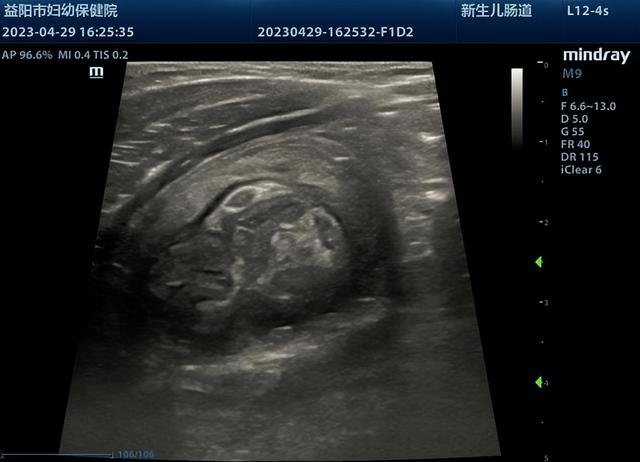

近日,一名仅11个月的小宝宝因呕吐1天来益阳市妇幼保健院就诊,经超声检查可见肠套叠特异征象“套筒征”及“同心圆征”,套入部分肠管长度较长,约60mm,诊断为回结型肠套叠。

超声实时监视下,见生理盐水缓缓充盈结肠至回肠套叠部位。由于患儿套入肠管较长,经操作医生辅以手法按摩,套入回盲部肠管缓慢退出,回盲瓣成功开放,小肠进液,复位成功。整个过程不到半小时。